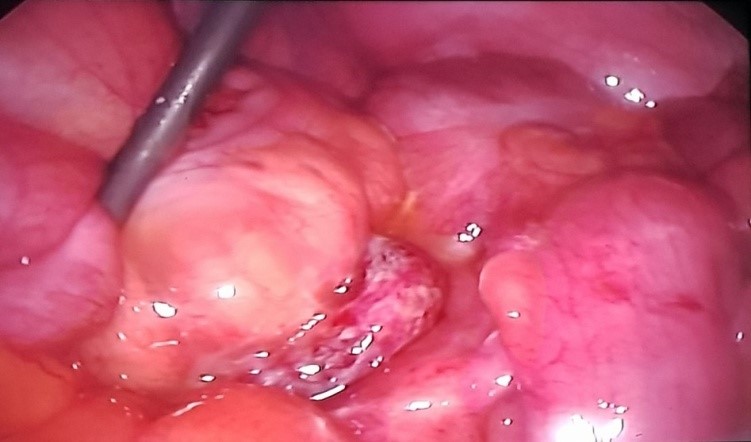

Bệnh nhân được mổ cấp cứu nội soi.  Vào ổ phúc mạc ghi nhận: Manh tràng quặt vào giữa ổ bụng, ruột thừa viêm mưng mủ toàn bộ nằm giữa ổ bụng sau đó đoạn đầu chui xuống tiểu khung. Tất cả ruột thừa được các quai ruột non và đại tràng xích ma che phủ bên trên. Ruột thừa được cắt hoàn toàn qua nội soi. Bệnh nhân hậu phẫu ổn định và xuất viện sau 5 ngày.

hình ảnh trong mổ

Hình 3. Hình ảnh trong mổ